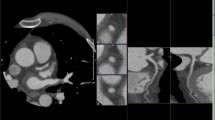

In comparison to coronary calcium scans, coronary CTA is an even more adept screening tool for CAD, given its ability to assess stenosis as well as myocardial disease and presence of infarction (Figs. 2 and 3). A 2009 comparison of coronary CTA to invasive coronary angiography showed sensitivity of 100%, specificity of 93%, positive predictive value (PPV) of 95%, negative predictive value (NPV) of 100%, and accuracy of 97% on a per-patient analysis in the general population for excluding CAD of greater than 50% luminal stenosis [11]. Other investigations by Pontone et al. and Maruyama et al. on coronary CTA in the general population have had comparable results [12, 13]. A fourth report did not complete a per-patient data analysis, but did describe similar sensitivity, specificity, accuracy, PPV, and NPV on a per-segment basis as 84.3%, 98.6%, 96.1%, 92.2%, and 96.9% [14]. With regard to the diagnostic performance and utility in patients with heart failure, a 2009 investigation concluded sensitivity of 100%, specificity of 96%, PPV of 0.9, and NPV 1.0 for > 50% luminal stenosis on a per-patient basis [15]. Papers by Andreini et al. (in 2007 and again in 2009), Ghostine et al., Polain De Warux et al., and Boulmier et al. have been published with concurrent results [16,17,18,19,20]. One possible complaint with these prior investigations is the relatively small patient population in the study. Yet, more recently, a larger (n = 537), multicentered prospective trial demonstrated that coronary CTA has sensitivity, specificity, NPV, and PPV of 92–100%, 83–93%, 88–100%, and 81–92%, respectively, for detection of > 50% luminal stenosis on per-patient model in the heart failure population [21].

One of the main ways to assess cardiac fibrosis is by measuring extracellular volume in the myocardium, which can be done with both late gadolinium enhancement with MRI and myocardial CT delayed enhancement (CTDE). The gold standard of non-invasive evaluation of myocardial scar from ischemia is cardiac MRI using a late gadolinium enhancement protocol with sensitivity, specificity, PPV, and NPV of 97.1%, 88.9%, 97.1%, and 88.9%, respectively [37]. Assessment of myocardial fibrosis via quantification of extracellular volume is possible with myocardial CTDE results which show strong correlations with both cardiac MRI and histological measures of fibrosis [38, 39]. Myocardial CTDE assessment of myocardial scar related to ischemia has an accuracy of 93–96% when compared with late gadolinium enhancement [37, 40, 41].

In addition to performing comparably to late gadolinium enhancement for evaluation of myocardial scar, a myocardial CT perfusion technique can detect hemodynamically significant CAD (Fig. 3) [51]. Myocardial CT perfusion can perform similarly to MRI stress perfusion, positron emission tomography, and single-photon emission computed tomography for detecting hemodynamically significant coronary artery lesions [52].